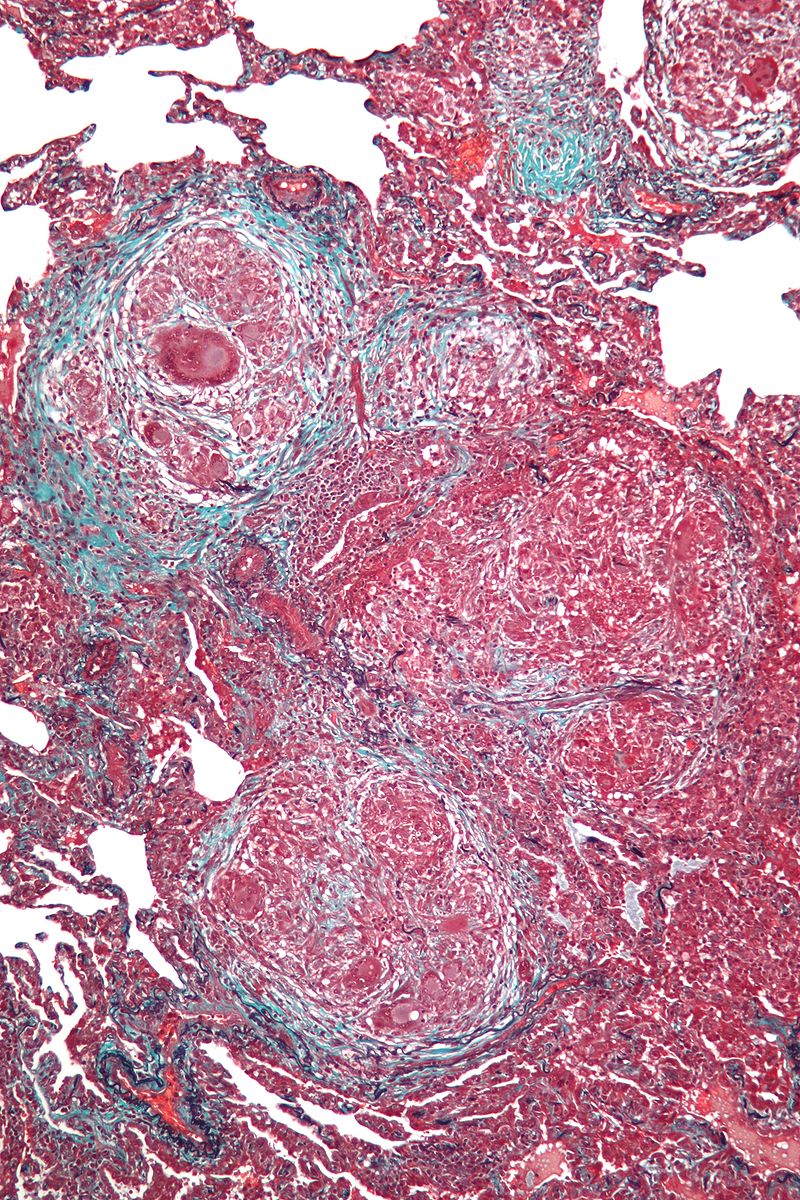

The granulomas mostly affect the hilar lymph nodes and lungs, causing restrictive lung disease.

Histology of sarcoidosis includes naked granulomas and stellate inclusions (‘asteroid bodies’) are often seen within giant cells of the granulomas.